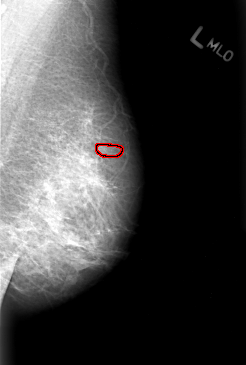

B_3007_1.LEFT_MLO

LEFT_MLO LINES 4376 PIXELS_PER_LINE 2952 BITS_PER_PIXEL 12 RESOLUTION 50 OVERLAY

FILE: B_3007_1.LEFT_MLO.OVERLAY

TOTAL_ABNORMALITIES 1

ABNORMALITY 1

LESION_TYPE CALCIFICATION TYPE PLEOMORPHIC DISTRIBUTION CLUSTERED

ASSESSMENT 4

SUBTLETY 3

PATHOLOGY MALIGNANT

TOTAL_OUTLINES 1

BOUNDARY